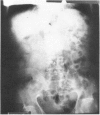

Images in this article